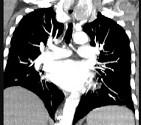

问题 40岁,女,发现颈部肿块,随吞咽上下移动,触之无搏动,咳嗽、气喘一周,请结合CT检查选择最可能的诊断()

选项 A.胸腺瘤 B.胸内甲状腺瘤 C.无名动脉瘤 D.无名动脉伸展扭曲 E.淋巴瘤

答案 B